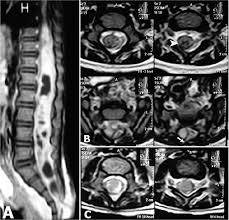

Chondromesenchymal Hamartomas In A 24 Year Old Male Mimicking A Posterior Mediastinal Tumor And A 5 Month Old Boy With Postoperative Disseminated Intravascular Coagulation Two Case Reports Diagnostic Pathology Full Text

Chondromesenchymal Hamartomas In A 24 Year Old Male Mimicking A Posterior Mediastinal Tumor And A 5 Month Old Boy With Postoperative Disseminated Intravascular Coagulation Two Case Reports Diagnostic Pathology Full Text from media.springernature.com